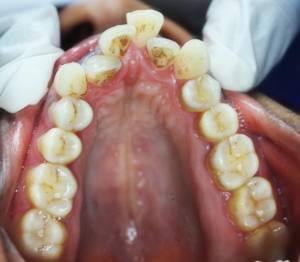

After Treatment (The Result)

After completion of orthodontic treatment, the patient showed:

• Properly aligned teeth

• Improved mouth closure

• A natural smile arc with improved esthetics, appearing even better than veneers

After-treatment images